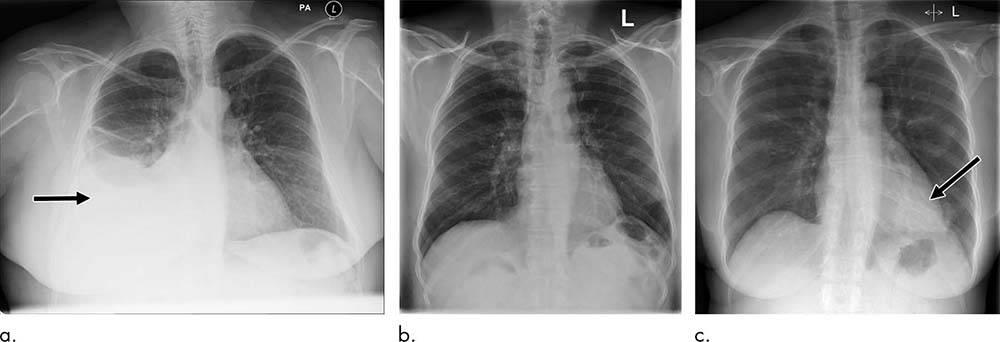

The NLP analyzed the radiologic report to prioritize each image as critical, urgent, non-urgent or normal. An AI system for computer vision was then trained using labeled X-ray images to predict the clinical priority from appearances only. The researchers tested the system’s performance for prioritization in a simulation using an independent set of 15,887 images.

The AI system distinguished abnormal from normal chest X-rays with high accuracy. Simulations showed that critical findings received an expert radiologist opinion in 2.7 days, on average, with the AI approach—significantly sooner than the 11.2-day average for actual practice.